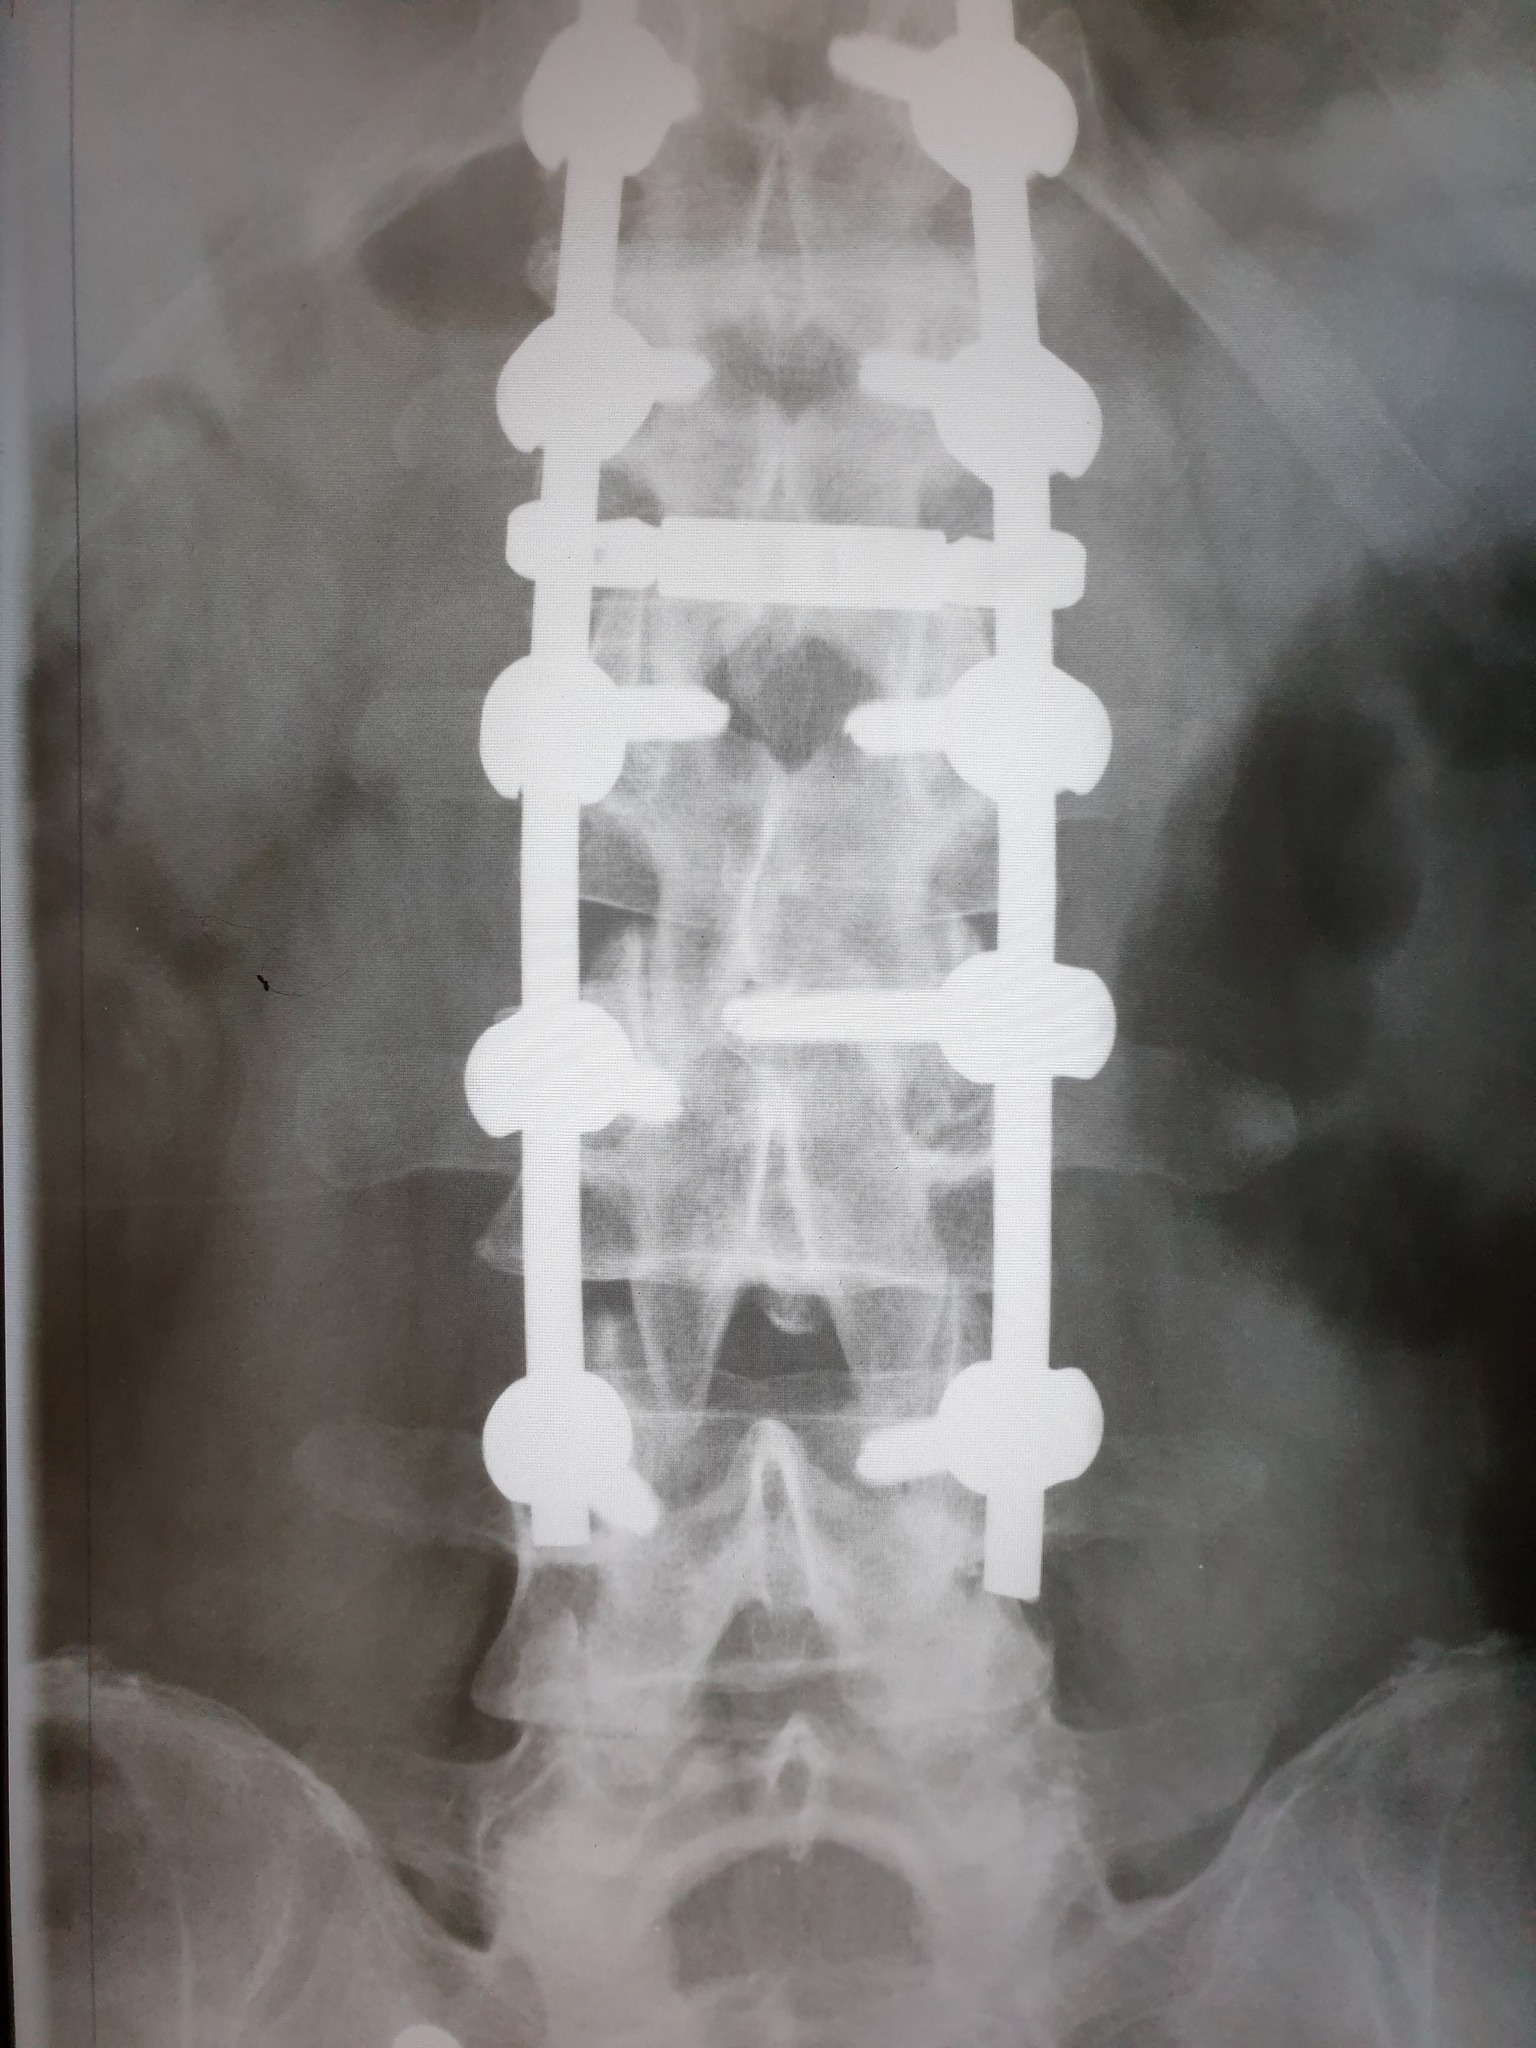

Nakon što je 11. februara doživio povredu na radnom mjestu, tačnije nakon što je pao sa lotri i slomio kičmu na dva mjesta Nino Katić je odlučio da progovori i sa svima podijeli svoje iskustvo, ali i pokaže zastrašujuće povrede koje je zadobio.

Šta dobiješ u “Centrumu” kada zbog njihovog neispravnog sredstva za rad slomiš kičmu na dva mjesta i ostaneš invalid? Pa kod neljudi dobiješ otkaz, i to poštom – rekao je Katić, a zatim je opisao šta je dovelo do teške nesreće koja se dogodila 11. februara, ali i svemu što je slijedilo nakon tog dana.

Došao je i 11. februar, taj crni 11. kada sam pao sa lotri, samo pukoše ispod mene i završio sam sa dvostrukim lomom kičme. Inspekciju nisu zvali, jedva je i Hitna pozvana, a kažu prva riječ šefova je bila: “Jeste li morali zvati Hitnu?”, Nakon toga me je zamjenica porodične doktorke oštetila svojim neradom jer mi nije htjela na vrijeme izdati uputnicu za ljekarsku komisiju na koju sam zbog toga zakasnio dva dana i uslijed čega mi je ljekarska komisija promjenila status iz “povreda na radu: DA” u “povreda na radu: NE”, znači svjesno se lagalo na zvaničnom dokumentu – objasnio je Katić za Srpskainfo.